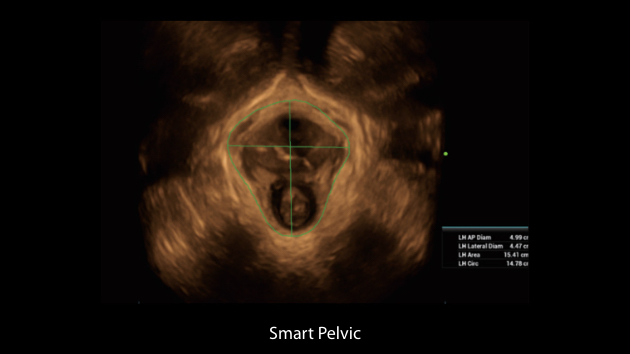

Intelligenza completa orientata allo scenario clinico

L'innovativa soluzione Smart Scene 3D consente l'identificazione automatica delle caratteristiche dei tessuti e fornisce una diagnosi specifica per i diversi distretti di esame durante l'intera procedura. Questa innovazione aumenta lŌĆÖaccuratezza e la sicurezza diagnostica, migliorando lŌĆÖefficienza.